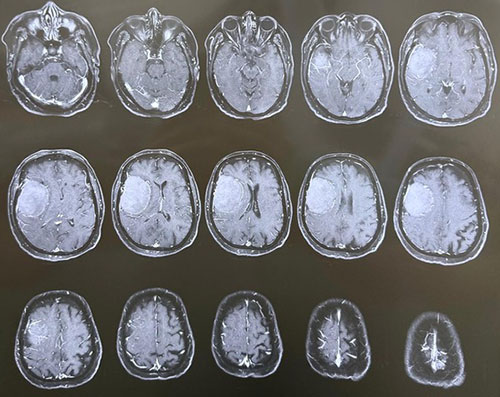

Dr. Ujwal Yeole is an experienced neurosurgeon specializes in treating a wide spectrum of neurological conditions including neuro-oncology, peripheral nerve disorders, vascular disorders, spinal pathologies, pediatric neurosurgery, neuro-trauma and skull base neuroendoscopic procedures.